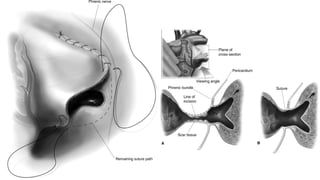

IC- TAPVC - ORIENTATION OF COMMON CHAMBER

SUTURELESS TECHNIQUE

Lacour Gayet